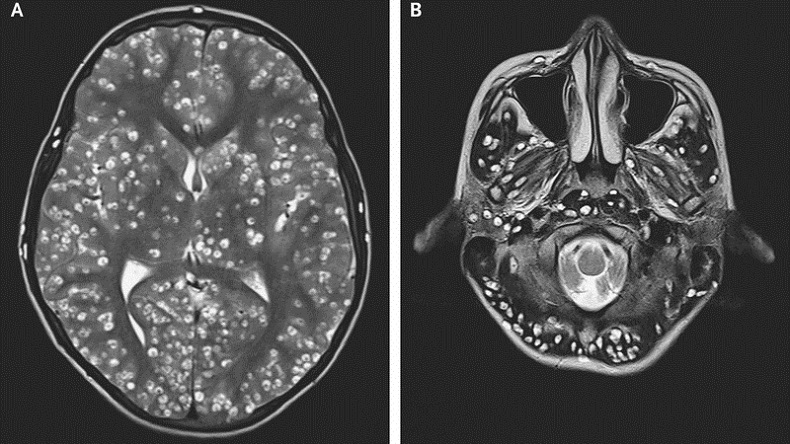

Su caso fue expuesto en la revista New England Journal of Medicine, en la que su médico explicó que tras los exámenes constataron graves lesiones quísticas cerebrales con cientos de larvas.

Pese a que lo diagnosticaron con cisticercosis, causada por larvas en su sistema nervioso central adquiridas tras comer el cerdo infectado, y a que el joven inició un tratamiento, murió dos semanas después.